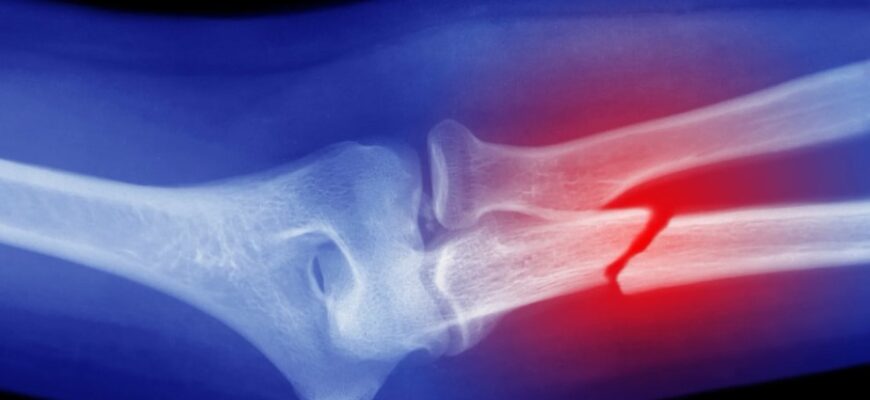

Діагностика: як виявляють перелом

Після первинних симптомів важливо звернутися до лікаря. Починається все з огляду, пальпації та опитування. Рентген стає наступним кроком, допомагаючи розглядати деталі. Якщо зображення не дає повної картини, не рідко застосовують КТ або МРТ. Комп’ютерна томографія точно покаже, а МРТ додасть інформацію про стан м’яких тканин.

Існує кілька способів класифікації переломів. По-перше, це стан шкіри: закритий (шкіра не пошкоджена, перелом непомітний) або відкритий (з видимими ранами та фрагментами кістки). Є різниця за напрямком лінії перелому: поперечні, косі, спіральні. Також розрізняють за ступенем ушкодження: повні (кістка повністю розділена) або неповні (просто тріщина).